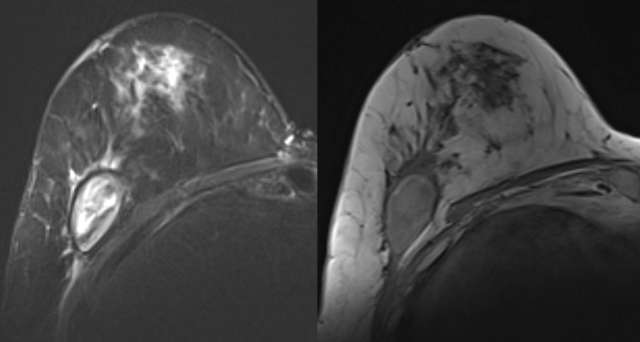

• MRI: Usually a well-defined, homogenous cystic lesion which is hyperintense on T2 and hypointense on T1.  Up to 25% have intrinsic T1 hyperintensity due to proteinaceous debris and/or heterogenous contents on T2 images, Figure 6.24

Case: Post-Surgical Fluid Collections Figure 6

Figure 6 - Seroma is noted on STIR and T1 MRI of the right breast. The fluid collection is STIR heterogenous and T1 hypointense suggesting predominantly simple fluid. Mild edema and post-surgical change is noted in the anterior breast.